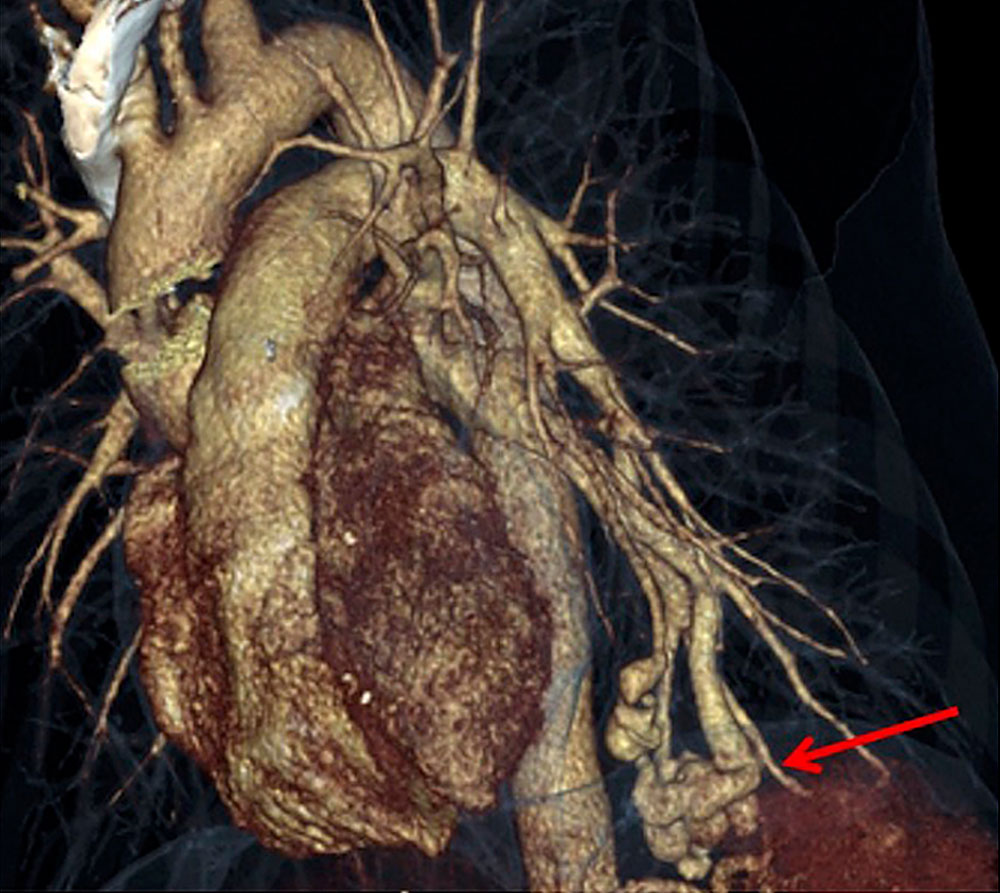

The vascular changes that develop on the basis of the genetic alterations in HHT can be very small in the form of dilated microvessels or several centimeters in diameter in the form of arteriovenous malformations (AVM) or fistulas. They occur in clusters at certain sites in the vascular system. Osler’s disease spots of the nasal mucosa can be identified clinically with relative certainty despite their various manifestations. Nasal endoscopic images show typical spots and their distribution in the nose.

Pulmonary arteriovenous malformations (pAVM) either attract attention because of dyspnea or, more dangerously, are discovered only as a result of brain abscess.

For hepatic vascular malformations (arteriovenous, arterioportal, and portovenous shunts), postprandial capsular pain is the typical symptom.